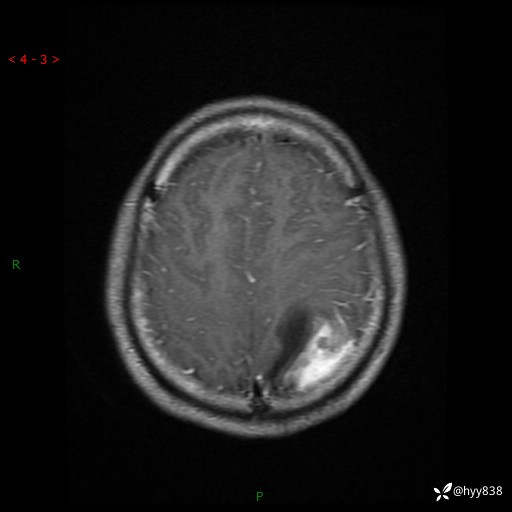

病例年轻小伙,头痛伴呕吐半年,渐进性加重1月。疑难病例,第一次见--结果公布~

性别:男

年龄:21岁

简要病史:头痛伴呕吐半年,渐进性加重1月

颅脑MRI平扫+增强